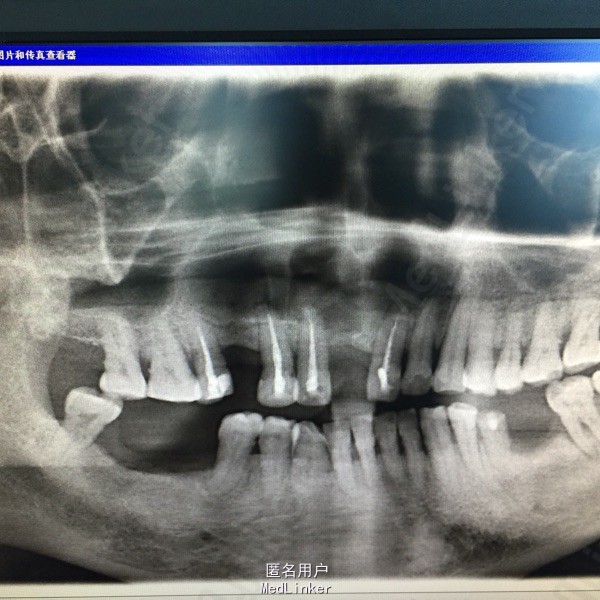

随访:患者自行用盐水冲洗创口,每半年复诊一次,全景牙片示:囊腔逐步减小,骨质形成。二年后复查囊腔大小约1x0.5cm。局部行囊肿挖除术。 讨论:囊肿开窗减压术,最大的保存愚者骨组织、患区牙保留。但需有良好的医从性。